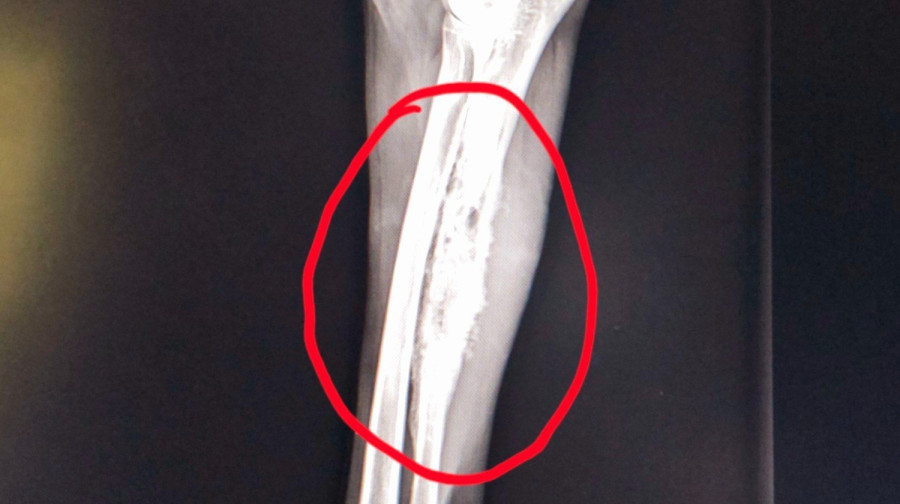

W rodzinie jest już ponad 10 lat. Niestety, niedawno lekarze zdiagnozowali u niego złośliwy nowotwór kości.

Guz rozwija się na przedniej łapie Pako, a mimo leków przeciwbólowych pies cierpi i kuleje.

Na szczęście badania nie wykazały przerzutów, ale czas działa na niekorzyść. Konieczna jest szybka amputacja łapy, by zapobiec dalszemu rozprzestrzenianiu się choroby.